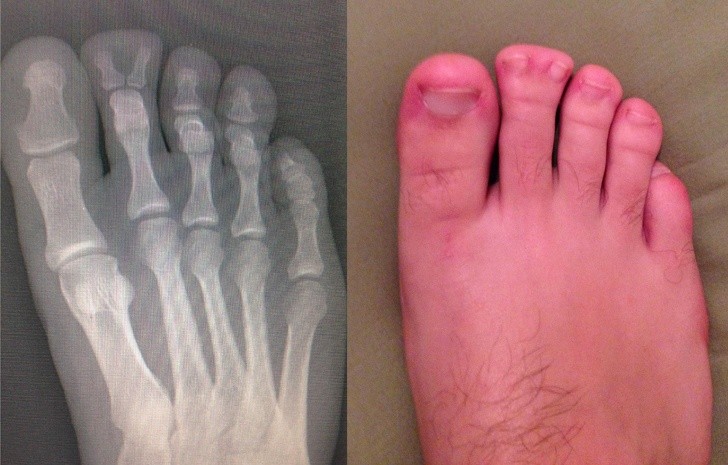

Ludzie to naprawdę dziwne stworzenia i mogą nam się przytrafiać niewiarygodnie dziwne rzeczy. Te prześwietlenia rentgenowskie zszokują nawet tych, którym wydaje się, że widzieli już wszystko.

Radiologi so tako že precej navajeni, da na rentgenskih posnetkih vidijo čudne stvari in nekatere izmed teh, ki smo jih za vas zbrali v galeriji, jih sploh niso presenetile. Tukaj je 15+ odštekanih in na trenutke šokantnih rentgenskih posnetkov.